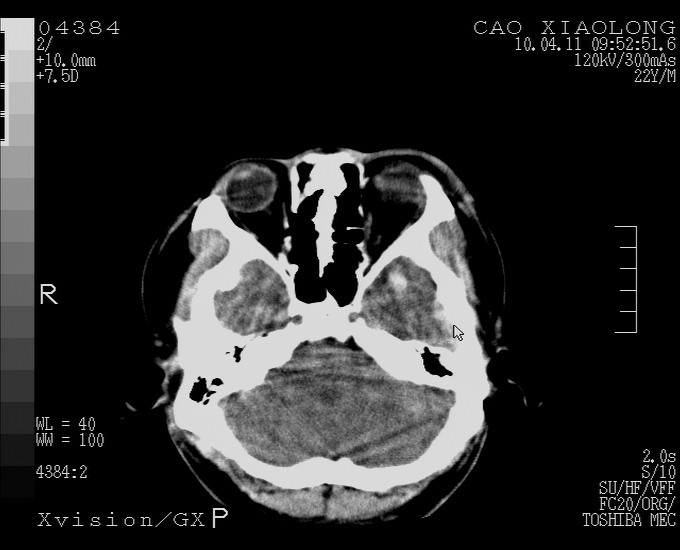

以下是引用随光逐影在2010-4-11 11:00:00的发言:[br]1)左侧额颞顶部硬膜下血肿。2)蛛网膜下腔出血。3)右侧颞顶部颅骨线形骨折。[br][br]20小时后复查:左侧额颞叶脑挫裂伤;左侧额颞顶部硬膜下血肿及蛛网膜下腔出血有吸收表现;右侧颞顶部颅骨线形骨折。[br]